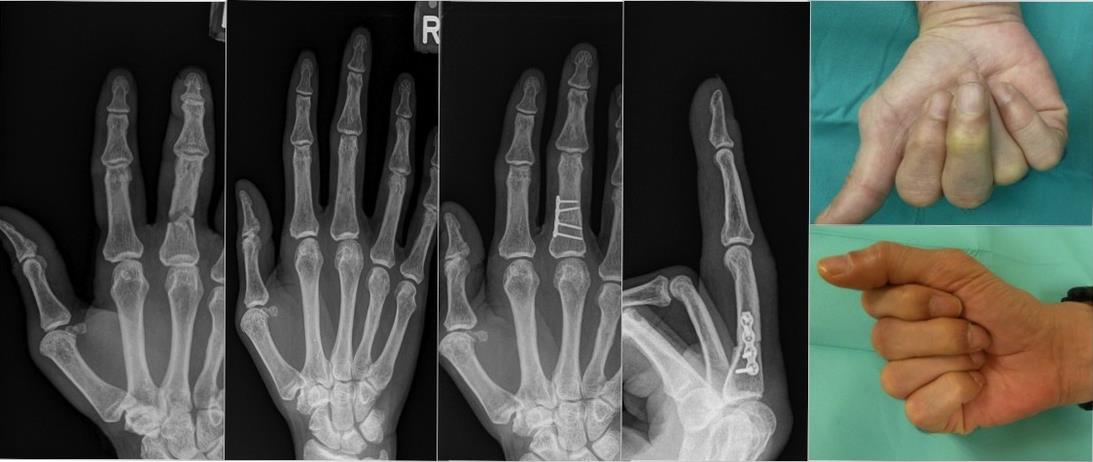

Post-traumatic Deformity

Post-traumatic Deformity from inadequate treatment of acute trauma represents another focus area of surgical expertise. Patients presenting with finger deviation or scissoring upon making a fist often exhibit malunion from a previous fracture. Following appropriate imaging assessments, our approach involve performing corrective osteotomies to improve the alignment and function of the fingers.

Figure 1: The above depicts the result of corrective surgery in a mal-united fracture of the phalanx of the middle finger.